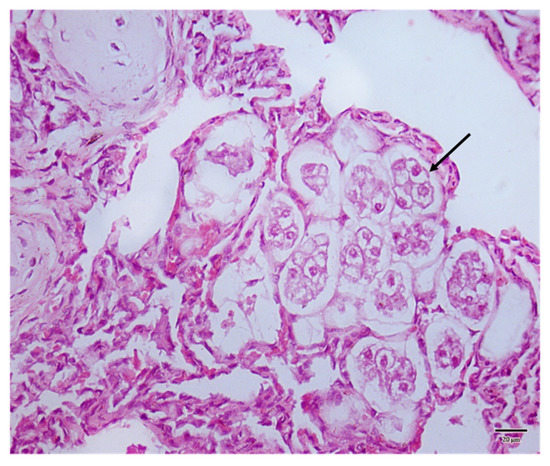

2.2. Necropsy and Histopathology